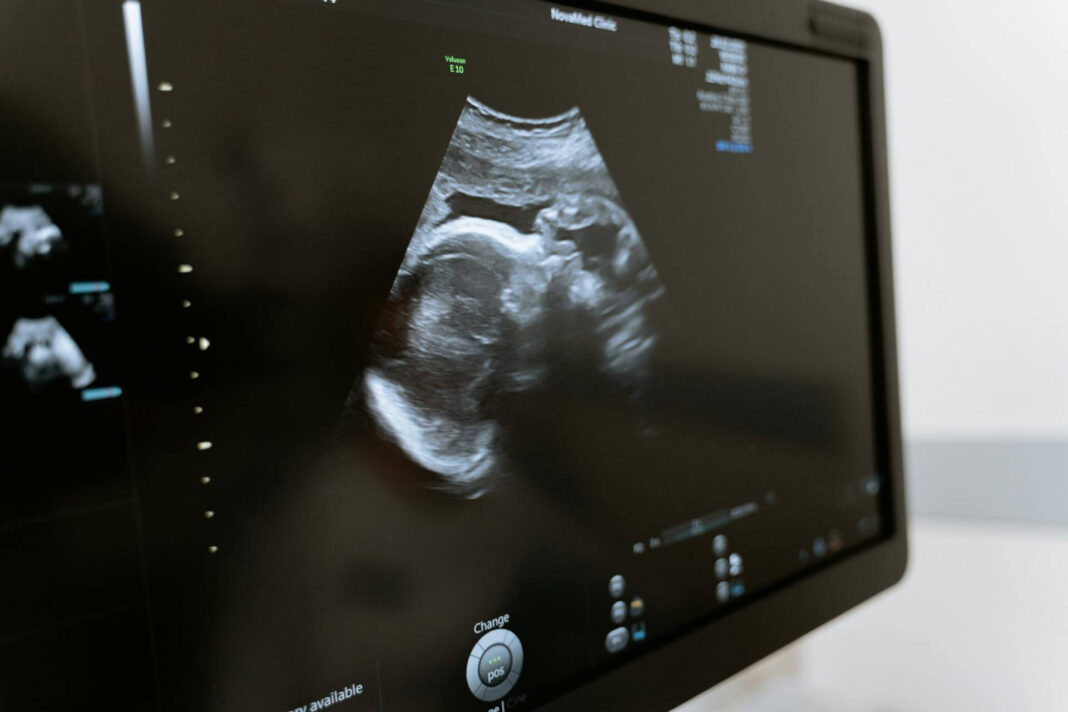

Echoskopija nėštumo metu yra vienas iš svarbiausių tyrimų, padedančių stebėti vaisiaus vystymąsi ir nėštumo eigą. Šis neinvazinis tyrimas naudoja ultragarso bangas, kad sukurtų vaisiaus ir gimdos vaizdus, leidžiančius gydytojams įvertinti kūdikio sveikatą ir nustatyti galimas problemas ankstyvoje stadijoje.

- Antrasis trimestras (18-22 savaitė): Tai yra pagrindinė echoskopija, vadinama anatomine echoskopija. Jos metu detaliai vertinamas vaisiaus vystymasis, organų struktūra, nustatoma lytis, vertinama placentos padėtis ir vaisiaus aplinkos būklė.

Echoskopija suteikia neįkainojamos informacijos apie kūdikio vystymąsi. Ankstyva diagnozė gali padėti laiku imtis reikiamų priemonių, taip apsaugant tiek motiną, tiek vaiką. Be to, echoskopijos metu tėvai gali pirmą kartą pamatyti savo kūdikį, kas suteikia ypatingą emocinį ryšį su būsima naujagimiu.